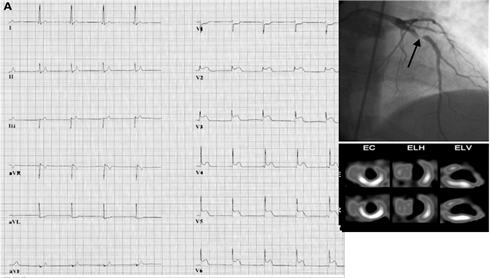

Los pulsos centrales y periférico eran palpables, simétricos y sincrónicos en frecuencia. La taquicardia supraventricular desapareció con la administración de dos dosis de Adenosine i.v. en bolus, con seis mg cada uno en un minuto (Figura 3).

Se realizó una descarga hospitalaria después de que el paciente cardiólogo se estabilizó por completo y se derivara de un paciente ambulatorio con el siguiente diagnóstico. Una taquicardia supraventricular paroxística y crisis de ansiedad: el paciente fue trasladado al Hospital porque tuvo un evento similar al expuesto, después de la primera visita con su cardiólogo ambulatorio. Allí, el paciente fue evaluado de forma adecuada con electrocardiograma, ecocardiograma, niveles sanguíneos de iones y marcadores cardíacos, así como estudio electrofisiológico (EEF) (Figura 4).

Fue negativo para niveles altos de troponina (I-T), CK, CPK-MB y, sin embargo, fue positivo para niveles bajos de ion de litio (<0.1 mEq/ L). A pesar de, un estudio profundo y cuidadoso de su electrocardiograma basal, se pudo evaluar la existencia de un corto intervalo PR y QTc.

A continuación, se presenta el primer electrocardiograma del paciente que pudimos evaluar. (A pesar de que se practican una serie completa de pruebas en el paciente, la más significativa en esta exposición es la electrocardiografía y los estudios de Holter) según se puede ver en la figura 3.

A 60 bpm se puede ver el corto intervalo PR (<0.120 segundos) junto con el corto intervalo QT (<0.350 segundos). Es especial en pistas inferiores y precordiales según se puede ver en la figura 4.

Las mismas características que la figura 1. Intervalo PQ: 0.100-0.110 segundos = Intervalo PQ corto. QTc (Bazzet) 0,339-0,340 segundos (<0,350 segundos) = Intervalo QT corto. QTc (Fridericia) 0,332 segundos (<0,350 segundos) = intervalo QT corto (Figura 5).

Este "Patrón de Breijo" lo hemos evaluado de forma aislada y asociado con otros tipos de enfermedades cardíacas. Tales como "Wellens Pattern", Wolf-Arkinson-White syndrome y en Takotsubo's Disease. Como se puede ver en las imágenes a continuación (Figura 6).

El "síndrome del corazón roto" (Takotsubo) y el Patrón de Breijo se aprecian correctamente en la siguiente imagen, 12,13) (Figura 7).